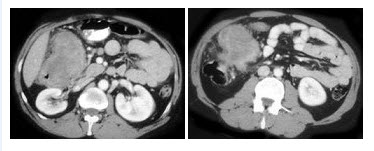

- 单项选择题男,42岁,左下腹可触及一长条形肿块,结合图像,最可能的诊断是()

- C